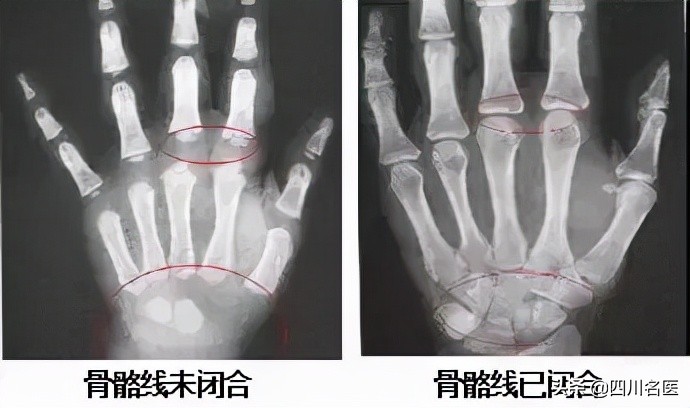

骨骺线还没有闭合

从长骨x片判断长骨骨骺是否闭合,一旦骨骺线闭合,人体就基本停止生长,这个时候打生长激素对长高是没有帮助的。